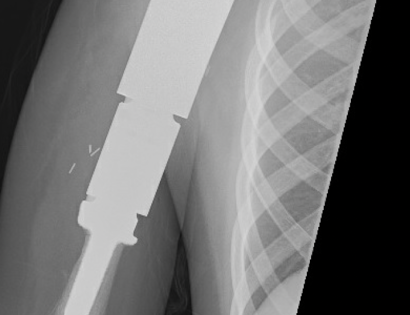

This is an x-ray image of the proximal humerus with the endoprosthesis fully inserted.